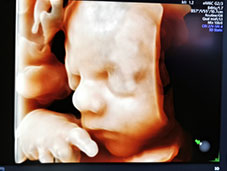

對于準(zhǔn)媽媽來說,腹中的胎兒是否健康牽掛著全家人的心,四維彩超是非常重要的篩查手段,可以清晰地看到胎兒是否有先天畸形,所以在孕期做四維彩超是很有必要的。另外,由于能夠查看到胎兒的活動,也能給準(zhǔn)爸爸媽媽帶來樂趣。

據(jù)統(tǒng)計,有80%的胎兒畸形都是在四維等B超排畸檢查中發(fā)現(xiàn)的,四維彩超能更直觀、清晰地展現(xiàn)胎兒在宮內(nèi)的動態(tài)圖像,多方位,多角度地觀察寶寶的生長發(fā)育情況。